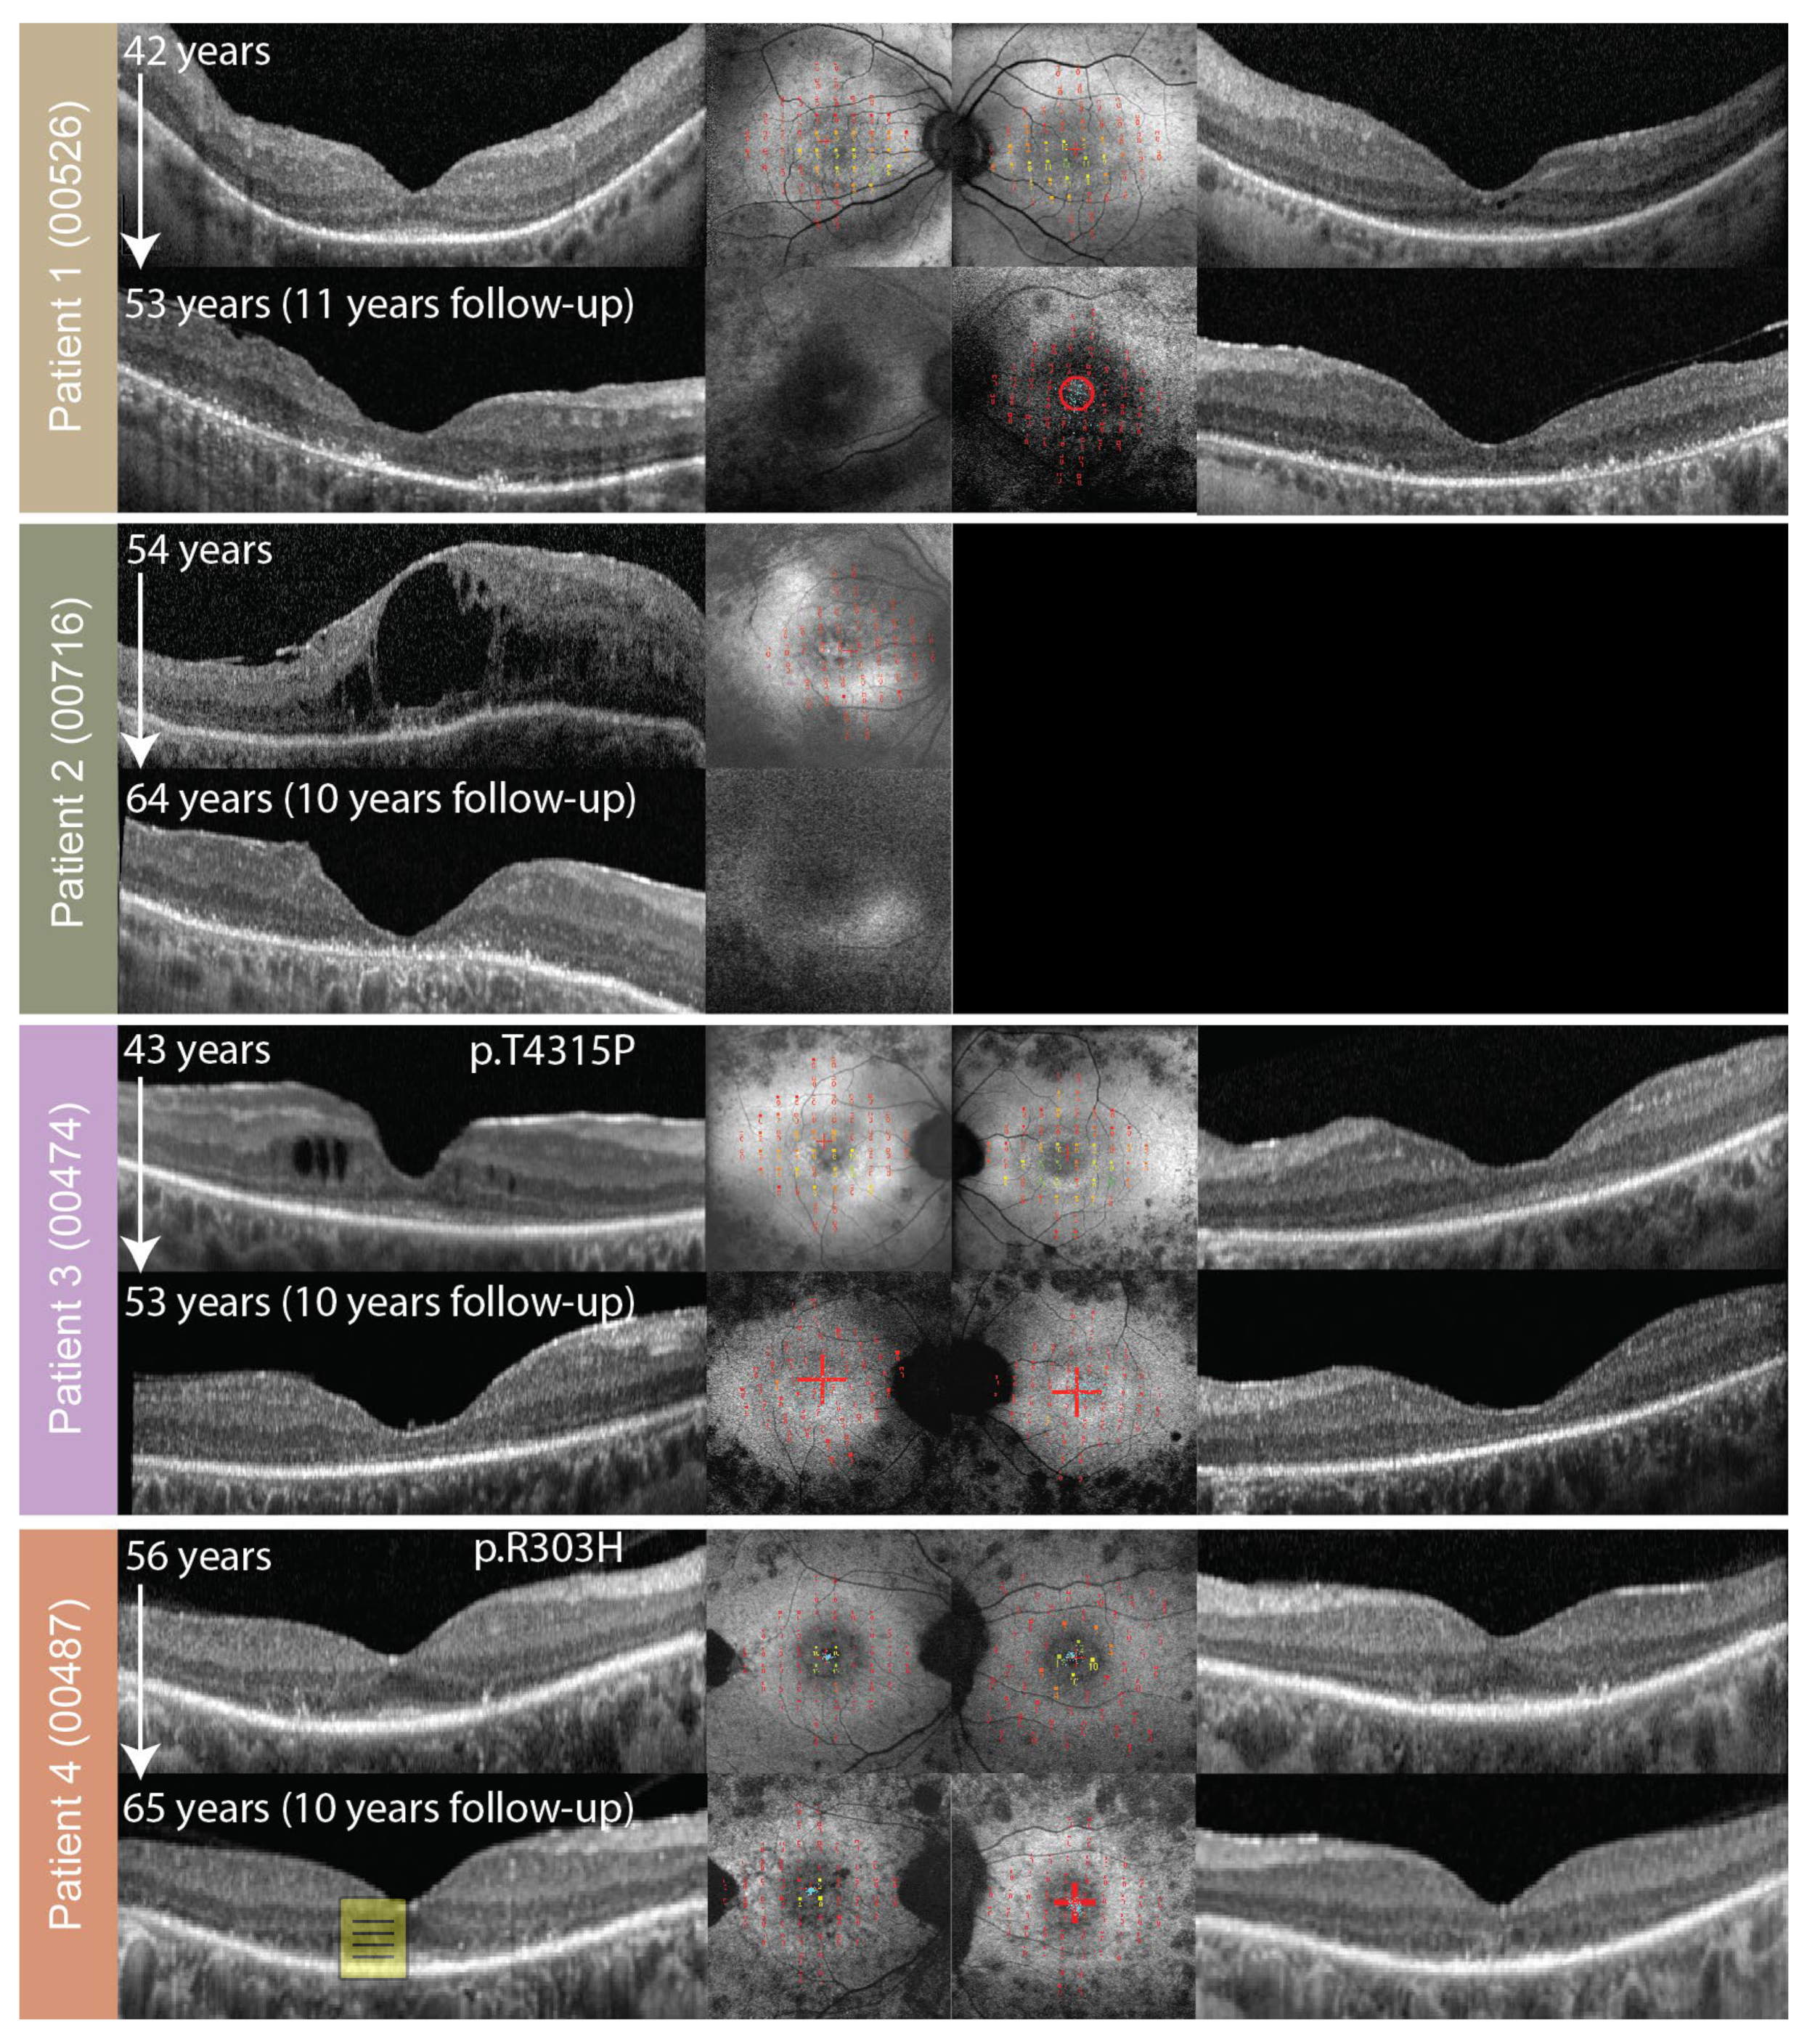

2.3. Fundus Autofluorescence and Optical Coherence Tomography

| 1’ | 00526 | 0321 | p.(Cys870*) | p.(Trp3955*) | Null |

| 2’ | 00716 | 0321 | p.(Cys870*) | p.(Trp3955*) | Null |

| 3 | 00474 | 0381 | p.(Cys870*) | p.(Thr4315Pro) | Non-null |

| 4 | 00487 | 0389 | p.(Cys870*) | p.(Arg303His) | Non-null |

| 1’ | F | 35 | 42 | 0.5 | 0.6 | 9 | 9 | 238; 23 | 360; 20 | 2.4 (44) | 2.9 (44) | Ring | Ring |

| 53 | CF | CF | 0 | 0 | 41; 7 | 109; 12 | 0.0 (54) | 0.0 (54) | Patch | Patch | |||

| 2’ | F | 8 | 43 | N/A | N/A | N/A | N/A | 343; 22 | N/A | 0.0 (54) | N/A | Patch (54) | N/A |

| 64 | N/A | 0.05 | 0 | N/A | 176; 15 (63) | N/A | N/A | N/A | Atrophy | N/A | |||

| 3 | F | 21 | 30 | 0.25 | 0.16 | N/A | N/A | 8225; 114 | 7316; 108 | 1.6 (39) | 3.6 (39) | Ring (43) | Ring (43) |

| 53 | 0.05 | 0.05 | 0 | 0 | 265; 18 | 665; 29 (48) | 0.1 | 0.1 | Patch | Patch | |||

| 4 | F | 22 | 56 | 0.9 | 0.8 | 1 | 1 | 3838; 65 (57) | 3477; 35 (57) | 0.8 | 1.1 | Ring | Ring |

| 65 | CF | 0.5 | N/A | N/A | 280; 20 | 194; 17 | 0.3 | 0.0 | Ring | Ring | |||